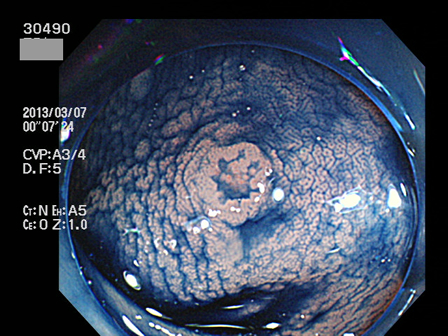

30400 30402 30405 30407 30408 30409 30413 30417 30419 30420 30422 30424 30428 30429 30432 30434 30442 30443 30444 30445 30446 30450 30451 30453 30458 30463 30464 30465 30467 30471 30472 30473 30474 30475 30476 30483 30487 30490 30492 30494 30496 30497 30499・・・・・・・の43名

上記100名より抽出した平坦・陥凹型腺腫(=癌化の危険が高いが見落としやすい病変)の内視鏡写真